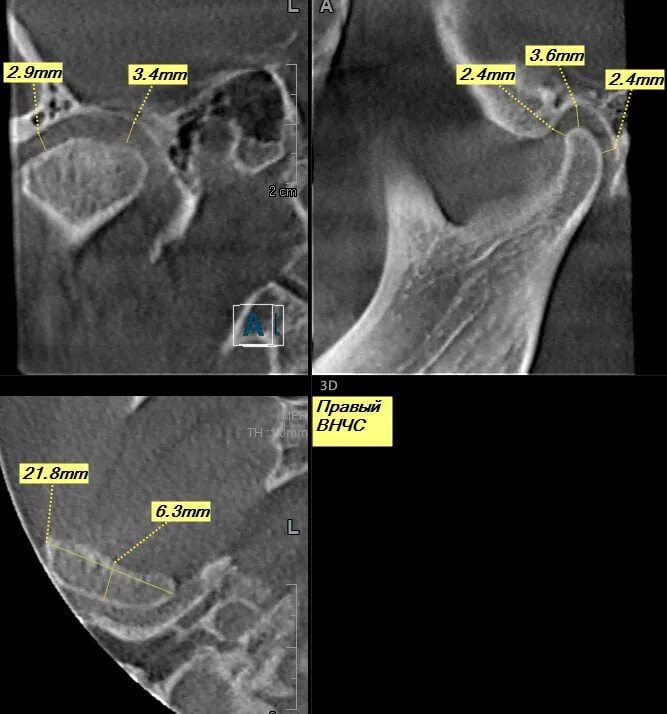

Дислокации дисков